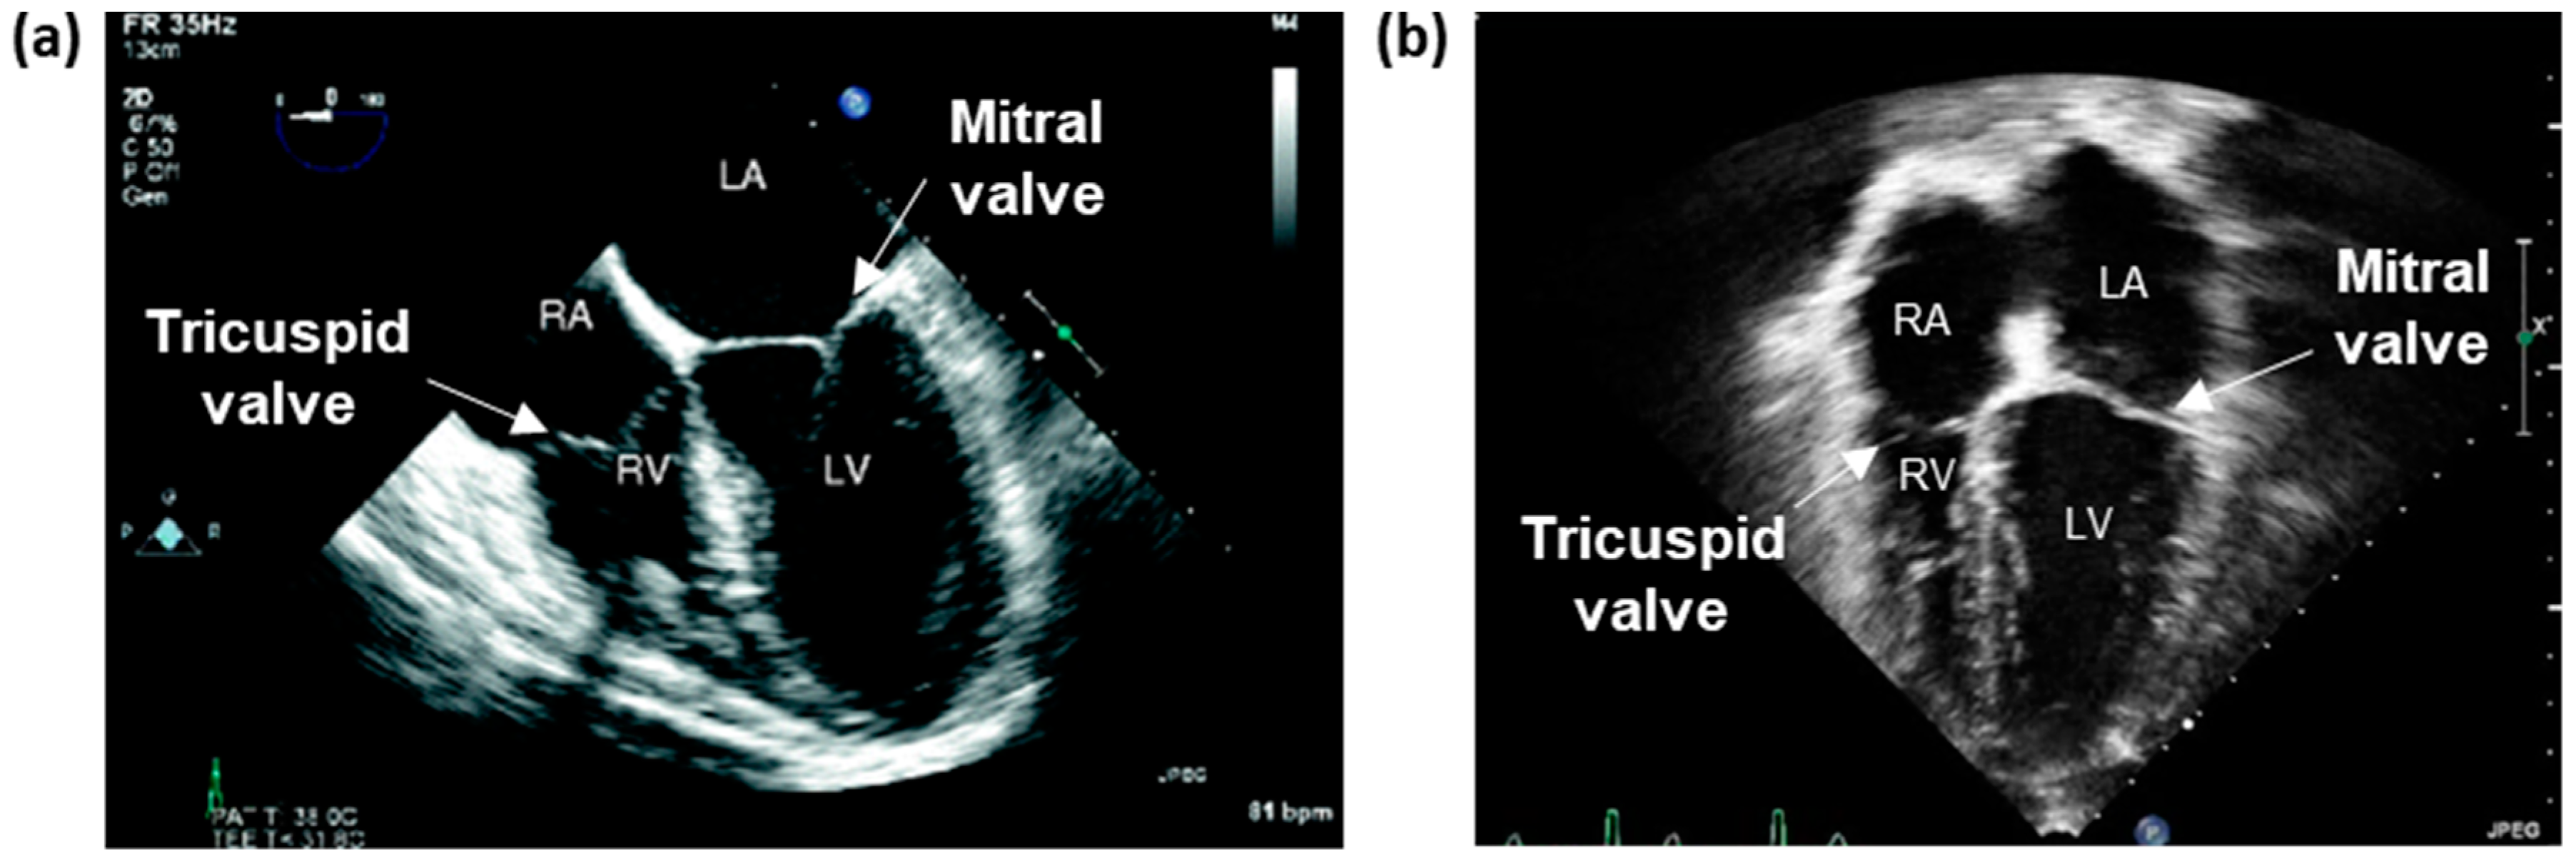

Two-Dimensional Imaging Modalities

Standard Echocardiography Imaging Windows

Three-Dimensional Imaging Modalities